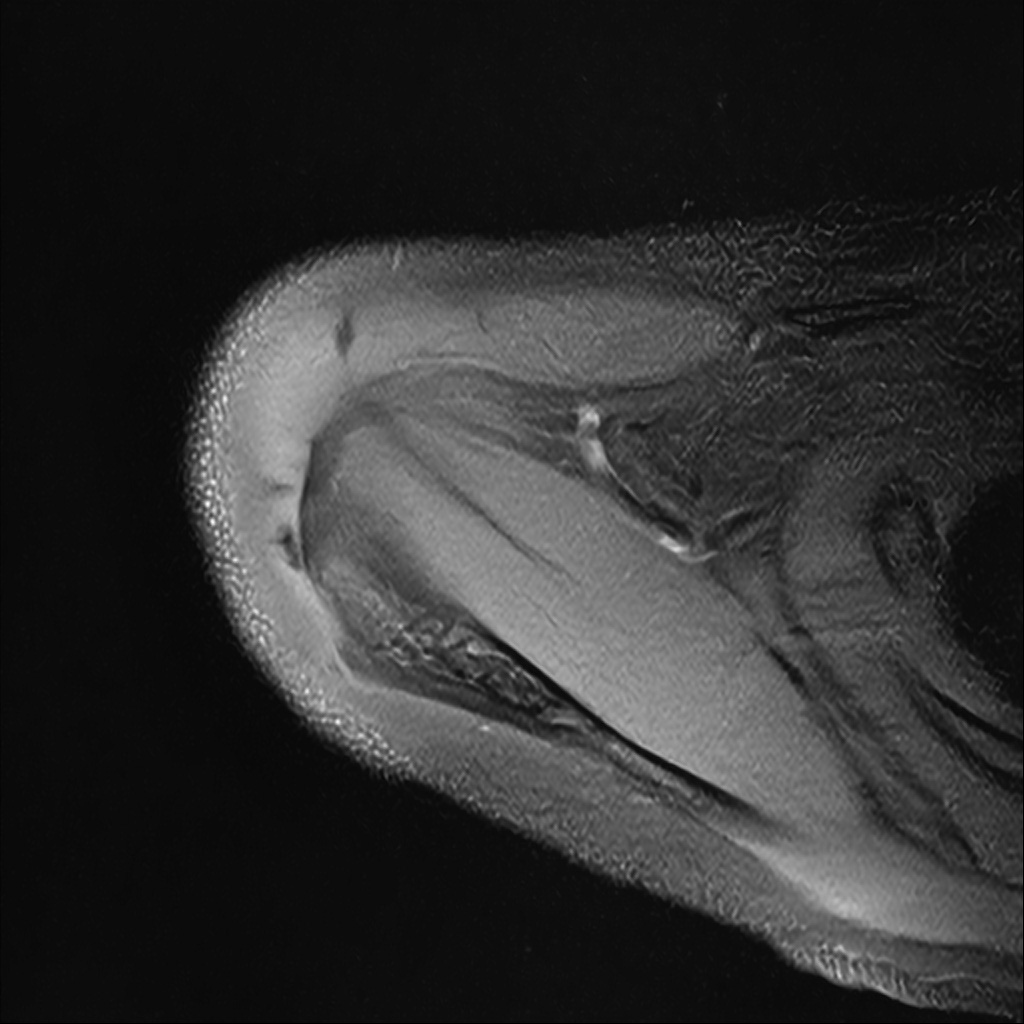

Mri 단면 영상으로 보아 어깨 관절 부위에서 이상 신호가 관찰되고 이는 관절 와순 파열의 가능성을 시사할 수 있습니다.

하지만 이영상만으로 정확한 진단은 불가능하고 정밀한 판단을 위해선 전체 시퀀스와 영상의학과 전문의의 공식판독이 필요합니다 특히 와순 파열은 위치와 동반 병변에 따라 해석이 달라집니다!